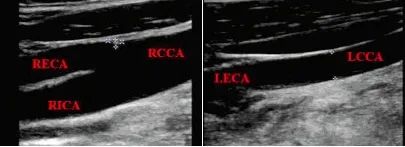

此時(shí)進(jìn)行頸部血管超聲檢查,發(fā)現(xiàn):雙側(cè)CCA管徑不對(duì)稱,RCCA管徑9.5 mm,向上分出RECA后,延續(xù)為RICA;LCCA管徑4.5 mm,向上未見分叉,直接延續(xù)為L(zhǎng)ECA,LICA管腔未顯影,如下圖,頸部血管超聲提示LICA先天未發(fā)育。